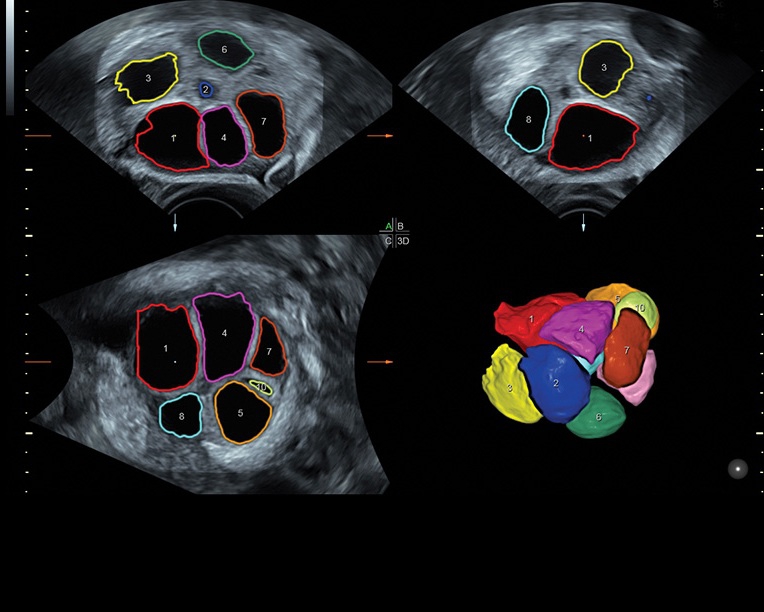

• Программа для исследований сердца плода с возможностью цветовых допплеровских и ангиографических исследований на основе анализа пространственно-временной корреляции изображений (STIС)

• Программное обеспечение для исследования сердца плода в режиме 3D/4D (быстрый доступ к плоскостям сканирования) по рекомендациям ISUOG

• VOCAL ™, SonoAVC (SonoAVC follicle, SonoAVCantral).SonoVCAD labor - программное обеспечение для исследования во втором периоде родов